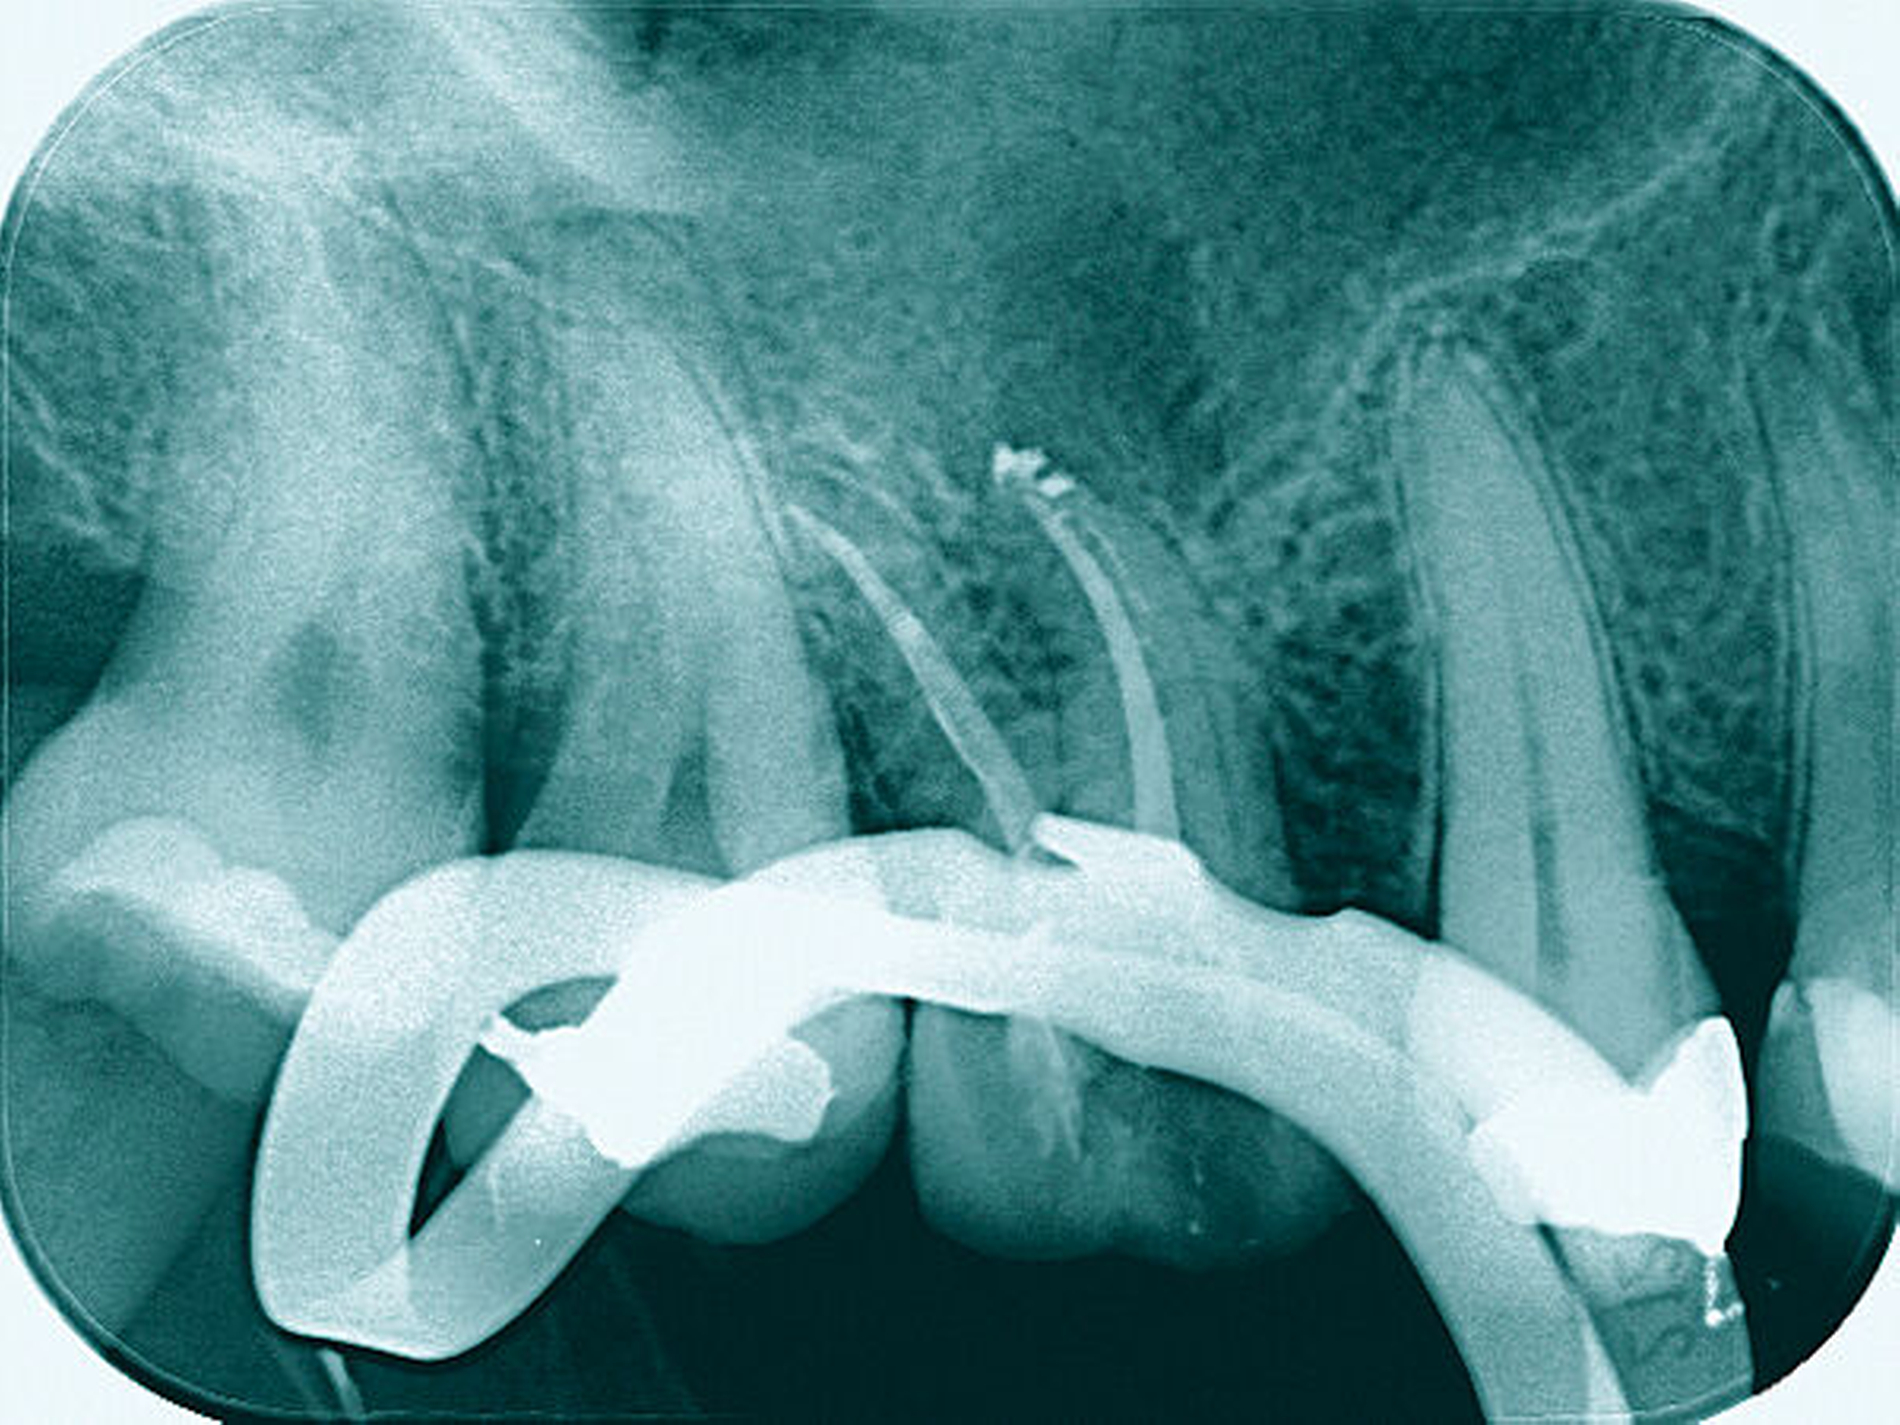

Nach der Anästhesie erfolgt bei einer beabsichtigten Entfernung einer der beiden bukkalen Wurzeln ein Ertasten der vestibulären Furkation. Wir halten es für ratsam, von der Furkation nach okklusal eine deutlich sichtbare Markierung mit einem wasserfesten Stift anzuzeichnen und diese Linie okklusal halbkreisförmig um die zu entfernende Wurzel zu verlängern. Das erleichtert die Orientierung beim Absetzen des zu entfernenden Zahnanteils. (Abbildung 1a).

Anschließend verwenden wir eine Lindemannfräse (H162SL, Firma Komet Dental, Lemgo) in einem Schnelllaufwinkelstück und trennen die Wurzel mitsamt des Kronenanteils vorsichtig entlang der zuvor angezeichneten Linie ab. Um den zu erhaltenden Zahnanteil nicht unbeabsichtigt mit der Fräse zu beschädigen, bleibt die Orientierungslinie zunächst unangetastet (Abbildung 1b).

Danach werden zunächst die dentogingivalen und die koronalen dentoalveolären Parodontalfasern der separierten Wurzel mit einem Periotom durchtrennt, anschließend wird die Wurzel mit Hebeln und Luxatoren gelockert. Falls erforderlich erfolgt die endgültige Entfernung mit einer Oberkiefer-Bajonettzange (Abbildung 1c).